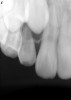

Figure 10  Clinical case of idiopathic resorption of the upper second bicuspid. The tooth was deemed hopeless and extracted.

Figure 10